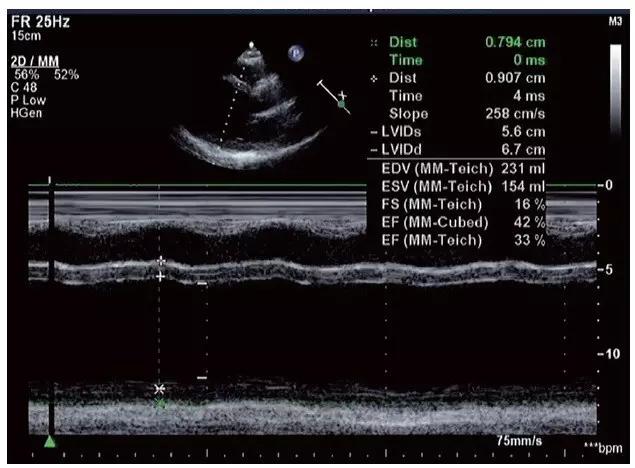

4.心脏收缩功能明显减低,射血分数(EF)≤ 30%,短轴缩短率(FS)≤ 15%,每搏输出量(SV)和心脏指数(CI)明显降低(图11-1-4)。

图11-1-4 扩张型心肌病心脏收缩功能明显减低